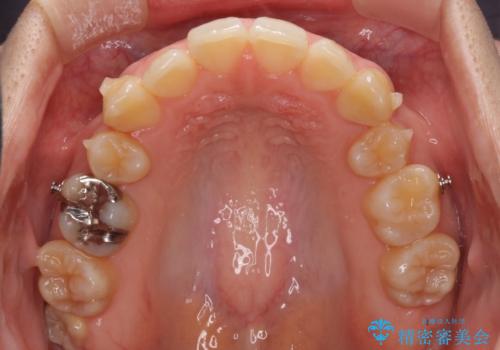

八重歯の抜歯矯正 補助装置を用いたインビザライン矯正

- 下の前歯のデコボコを気にして来院された患者様です。

来院当初、上顎の八重歯は気にしていらっしゃらなかったのですが、矯正治療をするのであれば、しっかりと治した方が良いと説明し、全顎矯正を行うこととしました。

八重歯の移動量が多く、インビザライン単体での治療は困難と判断し、補助装置により八重歯移動後にインビザラインを用いることとしました。

装着時間をしっかりと守ってくださったので、予定通りの期間で終了することができました。